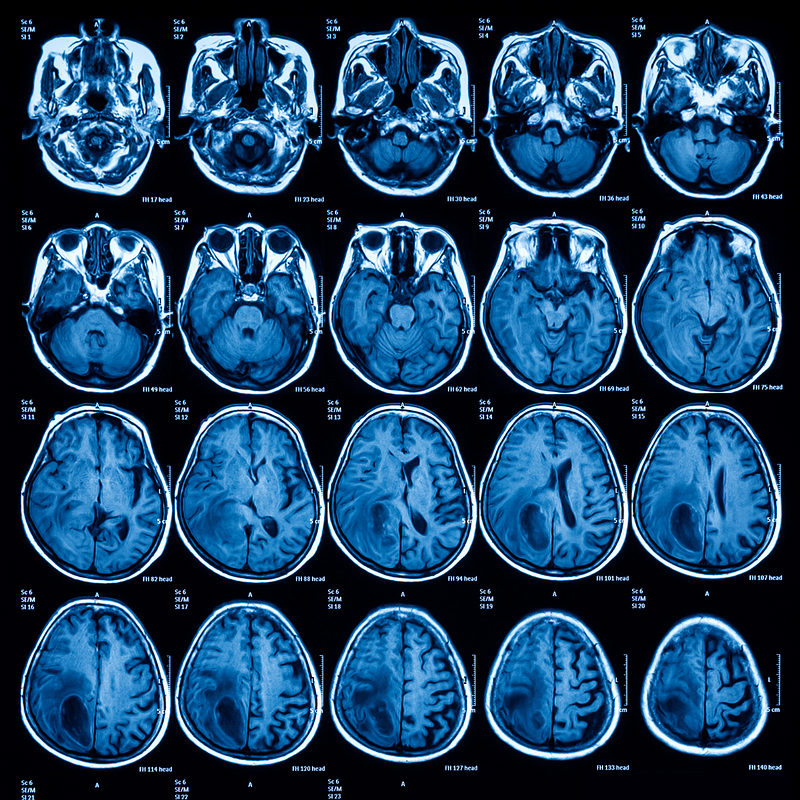

Resonancia cerebral

Ayuda a detectar anomalías, lesiones o enfermedades neurológicas.